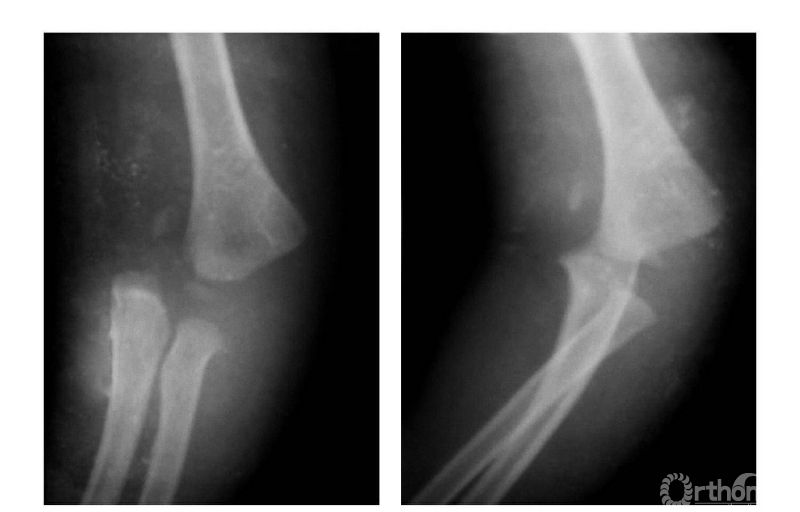

二、尺偏型

例:见肱骨小头及滑车骨骺伴前臂骨一同移向肘之尺侧,并略有旋转(图2)。

图2